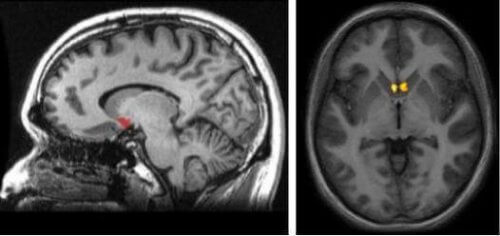

Où se trouve cette structure? Pour répondre à cette question, nous devons visualiser une aire sous-corticale (en-dessous du cortex) dans une zone d’interconnexion entre le noyau caudé, le putamen et le globus pallidus. Le plus intéressant à propos du noyau accumbens et sa localisation est qu’il fait partie de la voie dopaminergique du cerveau. On l’appelle la voie méso-limbique. Elle est chargée de nous stimuler chaque fois que notre cerveau comprend que nous vivons des expériences positives et gratifiantes.